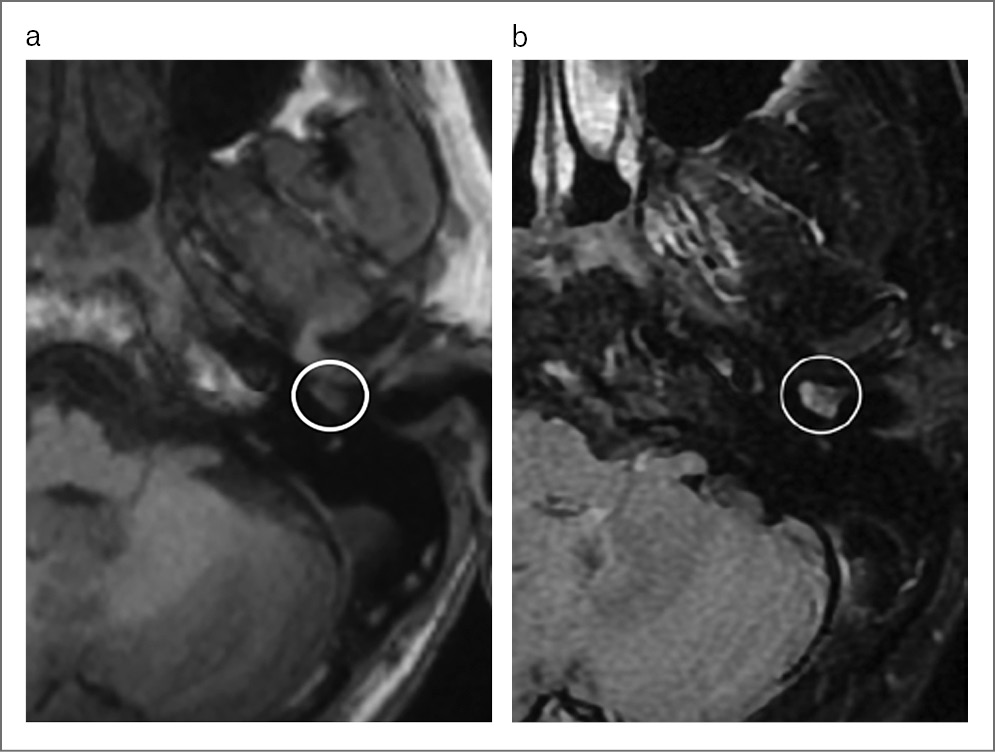

МРТ-семиотика неспецифична: новообразование показывает низкую или среднюю интенсивность сигнала на Т1-взвешенных изображениях (ВИ), высокую интенсивность сигнала на Т2-ВИ (рис. 3).

Рис. 3. МРТ головного мозга, сагиттальная проекция: a – Т1-ВИ, гипоинтенсивный сигнал от новообразования; b – T2-ВИ, изо-гиперинтенсивный сигнал от новообразования.

На КТ височных костей обычно в барабанной полости видна хорошо очерченная масса, без деструктивных изменений со стороны окружающей кости. По данным МРТ новообразование показывает низкую или среднюю интенсивность сигнала на Т1-ВИ, высокую интенсивность сигнала на Т2-ВИ и усиление сигнала после введения контраста. Новообразование может окутывать слуховые косточки, блокируя звукопроведение.